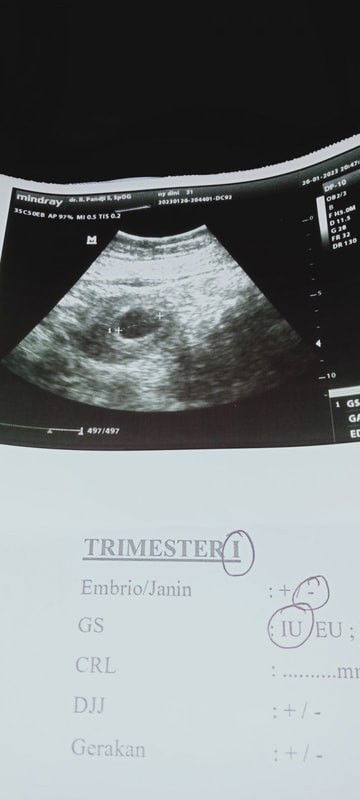

Hasil USG baru trlihat kantong saja d usia 6 week

Pagi Bun,mau tanya donk...aq kan hpht tgl 18 nov 2022,, Pas Desember tgl 30 aq tespek hasil nya garis 2 masih samar.aq tespek lagi tgl 1 Januari 2023 hasil masih samar jg.. Setelah itu aq coba tespek lagi tgl 10 Januari garis 2 sdh mulai kelihatan jelas. Skrg klo perhitungan kehamilan aq menurut hpht usia kandungan aq menginjak 11 Minggu. Tapi pas aq coba USG d tgl 26 Januari hasil USG nya kehamilan baru menginjak 6 Minggu,,dan hanya baru trlihat kantong kehamilan nya saja blm ada embrio/janin atau detak jantung nya. Karna sy penasaran sy coba USG ulang ke dokter kandungan yg lain di tgl 5 February,,USG transvaginal hasil USG ttp Bun,hanya baru trlihat kantong kehamilan aja..blm trlihat janin dan detak jntung. Gmn ya Bun,kira2 janin sy berkembang/tidak ya???jadi kepikiran dan was2.ada yg berpengalaman seperti sy ga ya? trs#ingintahu #firstmom #pleasehelp #fibroid #seriusnanya